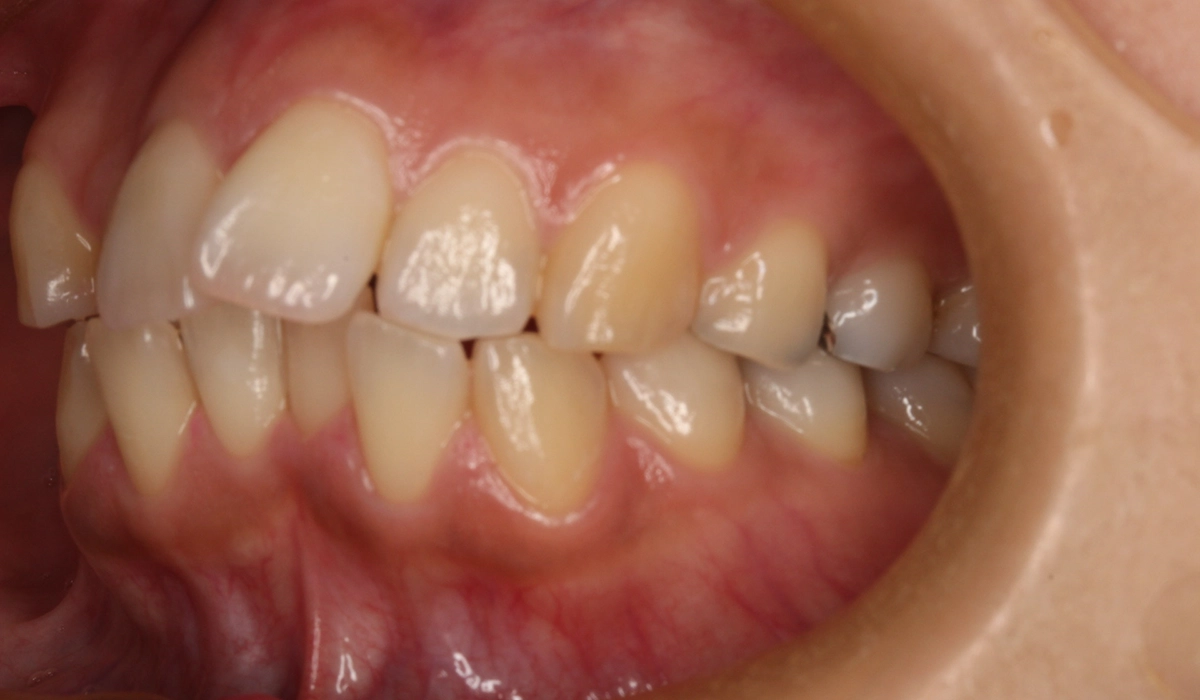

術前:右側

術後:右側